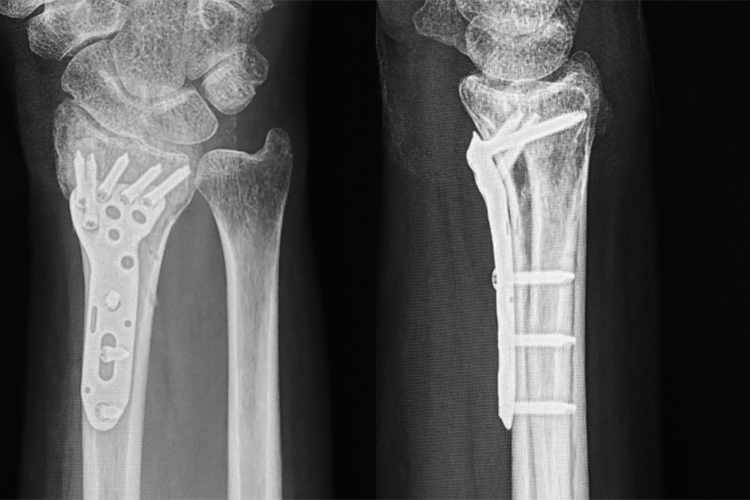

橈骨、尺骨遠位端骨折といった手首の骨に対するプレート固定

外傷でも最も多いのは骨折で、代表的なものは高齢女性に好発する橈骨遠位端(とうこつえんいたん)骨折、転倒して手をついた時に骨粗しょう症によって脆弱になった手首の骨が折れてしまうケースです。手術によってずれた骨を整復しプレートで固定します。肘関節脱臼骨折は治療の難しい外傷で、手術で正確に関節面を整復することが鍵となります。また、刃物やガラスの破片で指を切ると、腱や神経が切れることもあります。指を曲げる屈筋腱は、かつては治療が難しいものとされていましたが、最近では精密な手術と早期のリハビリテーションで良好な結果が望めるようになりました。また、野球肘などスポーツ障害に対しても積極的に取り組んでいます。